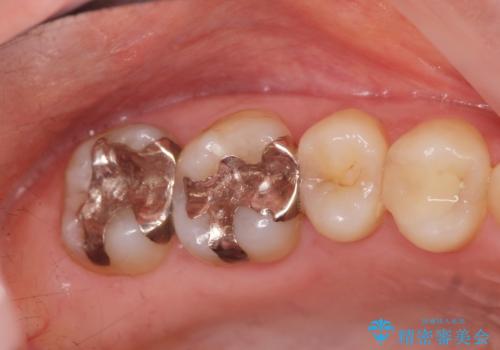

メタルフリー治療 銀歯を全て除去したい

- 口腔内の金属、銀歯を全て除去しセラミックにしたい。と、希望され来院されました。

口腔内の金属を丁寧に除去したのち、精度・審美性に優れるセラミック治療を計画します。